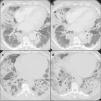

A negative nasopharyngeal-throat swab excluded the SARS-CoV2 infection. The erythro-sedimentation rate was high (64 mm), whereas the C-reactive protein, the procalcitonin, the total leukocyte count and the renal and hepatic function were normal. The first chest high resolution computed tomography (HRCT) showed diffuse and bilateral ground glass opacities with thickened interlobular septa all over the lungs, which were suggestive of an infectious disease. For this reason, we started an empiric antibiotic therapy with amoxicillin/clavulanic acid and subsequently with levofloxacin, in association with oxygen supplementation (Fig. 1). No positivity was revealed on gargled samples for bacteria, viruses or other germs.

The patient presented a rapid worsening of respiratory failure needing support with high flow nasal oxygen (HFNO). Pneumocystis jirovecii was isolated in broncho-alveolar lavage (BAL) with a low replication load, so we increased the antibiotic therapy with trimethoprim/sulfamethoxazole. Because of disease severity vancomycin was also added to cover nosocomial pathogens. The BAL cellular analysis resulted nonspecific: it revealed mostly foamy macrophages.

Nevertheless, the patient's clinical and radiological features continued to deteriorate. The patient was transferred to the Intensive Care Unit where non-invasive mechanical ventilation was added to HFNO due to clinical deterioration with associated respiratory failure and also radiological worsening with finding of increased ground glass opacities in the chest HRCT scans.